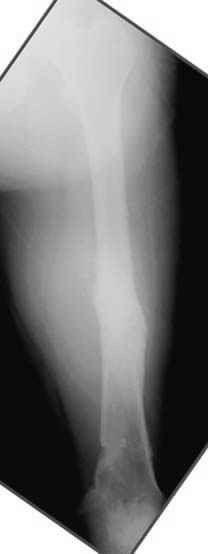

На рисунке N1 предоперационный план лечения ложного сустава шейки бедра- линия ложного сустава, угол и направление введения импланта, клиновидная остеотомия в градусах и миллиметрах, второй снимок после коррекции, расчет, на сколько удлиняется конечность и размеры импланта;

N3 рисунок окончательный снимок, после операции моя рентгенограмма должен выглядеть примерно как эта картина. На N4 снимке клин перед удалением; N5 послеоперации 3 нед.; N6 окончательная рентгенограмма.

Отправитель: Djoldas Kuldjanov 23 Ноябрь 2004, 18:21

пластическая модель; и коррекция бедра аппаратом Илизарова.